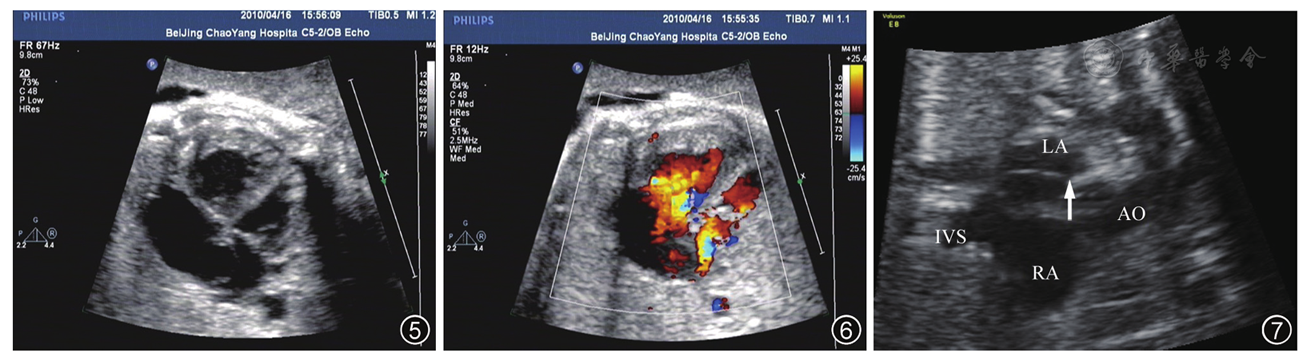

图4 彩色多普勒血流成像示下腔静脉血流回流入右心房朝向卵圆孔大部分流入左心房

图7 孕40周胎儿主动脉弓双心房切面示卵圆孔瓣闭合(箭头所示)